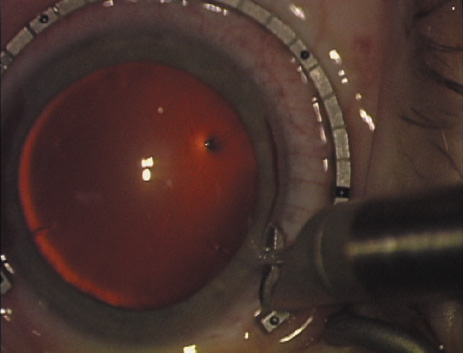

ways. Our preferred method makes use of a modified Fine-Thornton fixation

ring (Nichamin Fixation Ring and Gauge; Mastel Precision, Storz, Rhein

Medical). This instrument serves to fixate and position

the globe in order to optimize incision placement, as well as to delineate

the extent of arc to be incised. One visually extrapolates from

the limbus to marks on the surface of the ring. Each incremental mark

is 10 degrees apart, and bold hash marks (180 degrees) opposite

to each other serve to align and center the incision over the steep

meridian. This approach obviates the need to ink and physically mark

the cornea. If one desires, particularly when first gaining experience

with LRIs, a two-cut RK marker may be used to place ink marks upon the

cornea to show the exact extent of arc that is to be incised, in conjunction

with the fixation ring/gauge (Fig. 4). Alternatively, various press-on markers are available, such as

markers, rings, and blades for performing LRIs.  Fig. 4. The Nichamin Fixation Ring and Gauge serves to both fixate the globe and

delineate the extent of arc to be incised; a two-cut radial marker may

be used to mark the extent of arc to be incised, and the Mastel Nichamin

Force AK Diamond Blade with preset depth of 600 microns. Fig. 4. The Nichamin Fixation Ring and Gauge serves to both fixate the globe and

delineate the extent of arc to be incised; a two-cut radial marker may

be used to mark the extent of arc to be incised, and the Mastel Nichamin

Force AK Diamond Blade with preset depth of 600 microns.